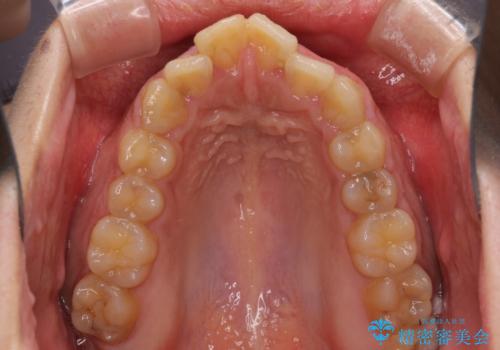

- 口元の突出感と上下前歯のでこぼこを気にして来院された患者様です。

上下前歯部叢生のスペース獲得のため、上下顎左右小臼歯各1歯(計4本)を抜歯して、矯正治療を行うこととしました。

口腔内の清掃性に問題があり、虫歯のリスクが極めて高かったため、短期で治療を終えることを最優先に治療を進めました。